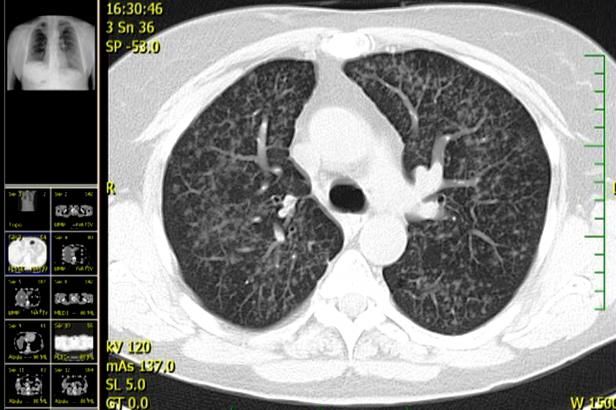

obrázek: Imunoterapie – nová éra v léčbě rakoviny plic, říkají lékaři